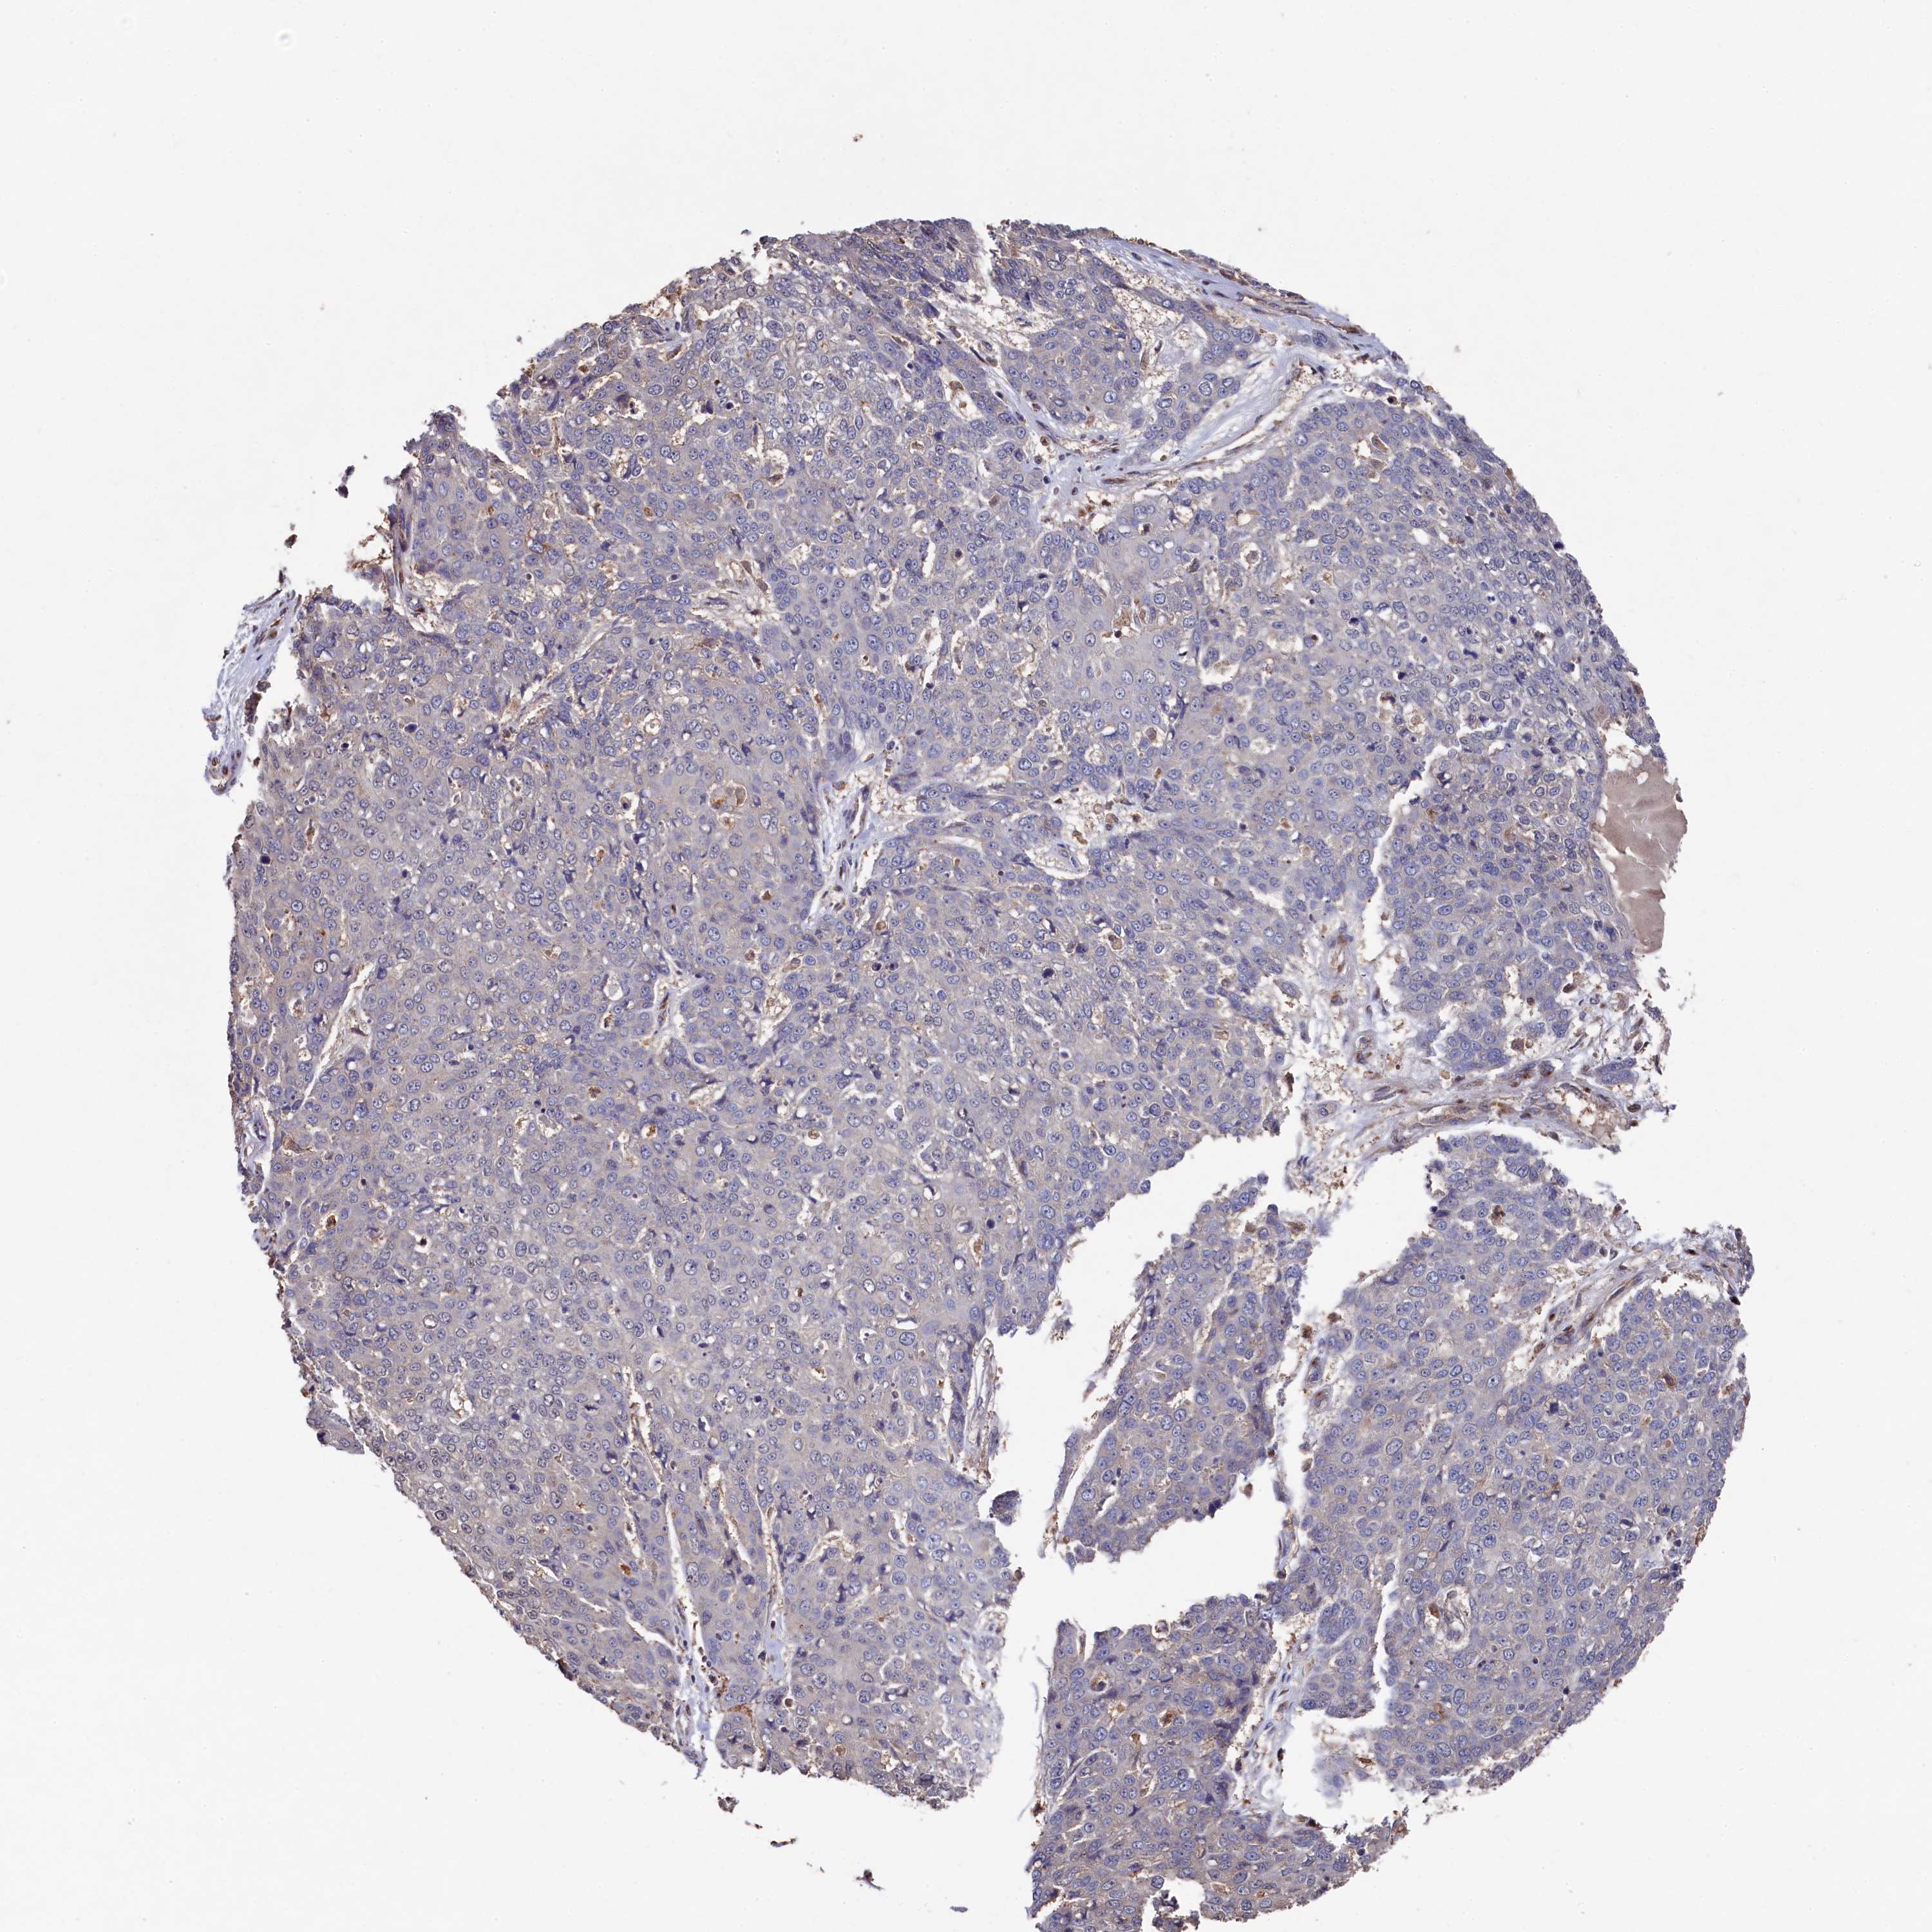

CANCER SKIN CANCER Show tissue menu

Basal cell and squamous cell cancer

SKIN CANCER - Protein expressioni

A mouse-over function shows sample information and annotation data. Click on an image to view it in a full screen mode. Samples can be filtered based on level of antibody staining by selecting one or several of the following categories: high, medium, low and not detected. The assay and annotation is described here.

Each image is clickable and will lead to virtual microscopy that enables deeper exploration of all samples and also displays staining intensity scores, fraction scores and subcellular localization as well as patient and tissue information for each sample.

Antibody HPA040916

Basal cell carcinoma

Squamous cell carcinoma, NOS

Squamous cell carcinoma, metastatic, NOS